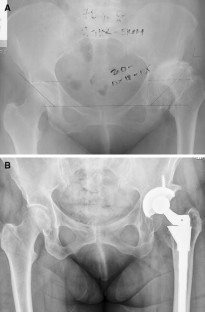

Fig. 3A–B